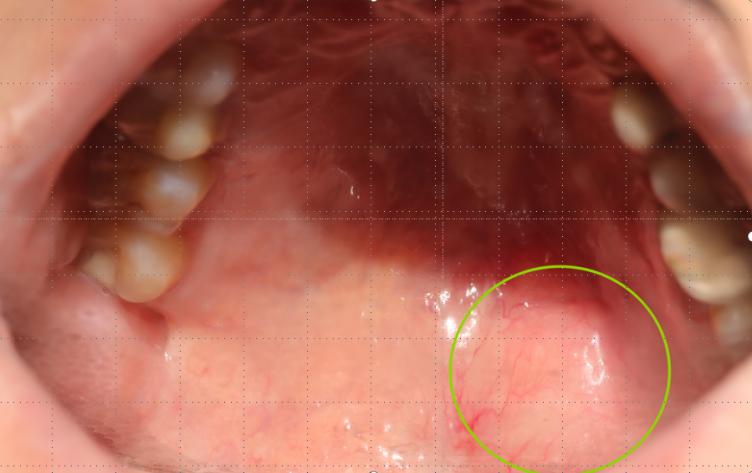

入院检查发现,在傅女士左侧软硬腭交界处的黏膜上,有一个约2.5x1.5厘米的膨隆,表面光滑,触诊无明显不适。医疗团队为其施行了“腭部肿物扩大切除术”,将肿物完整切除。术后病理诊断结果却令人后怕:腺样囊性癌。